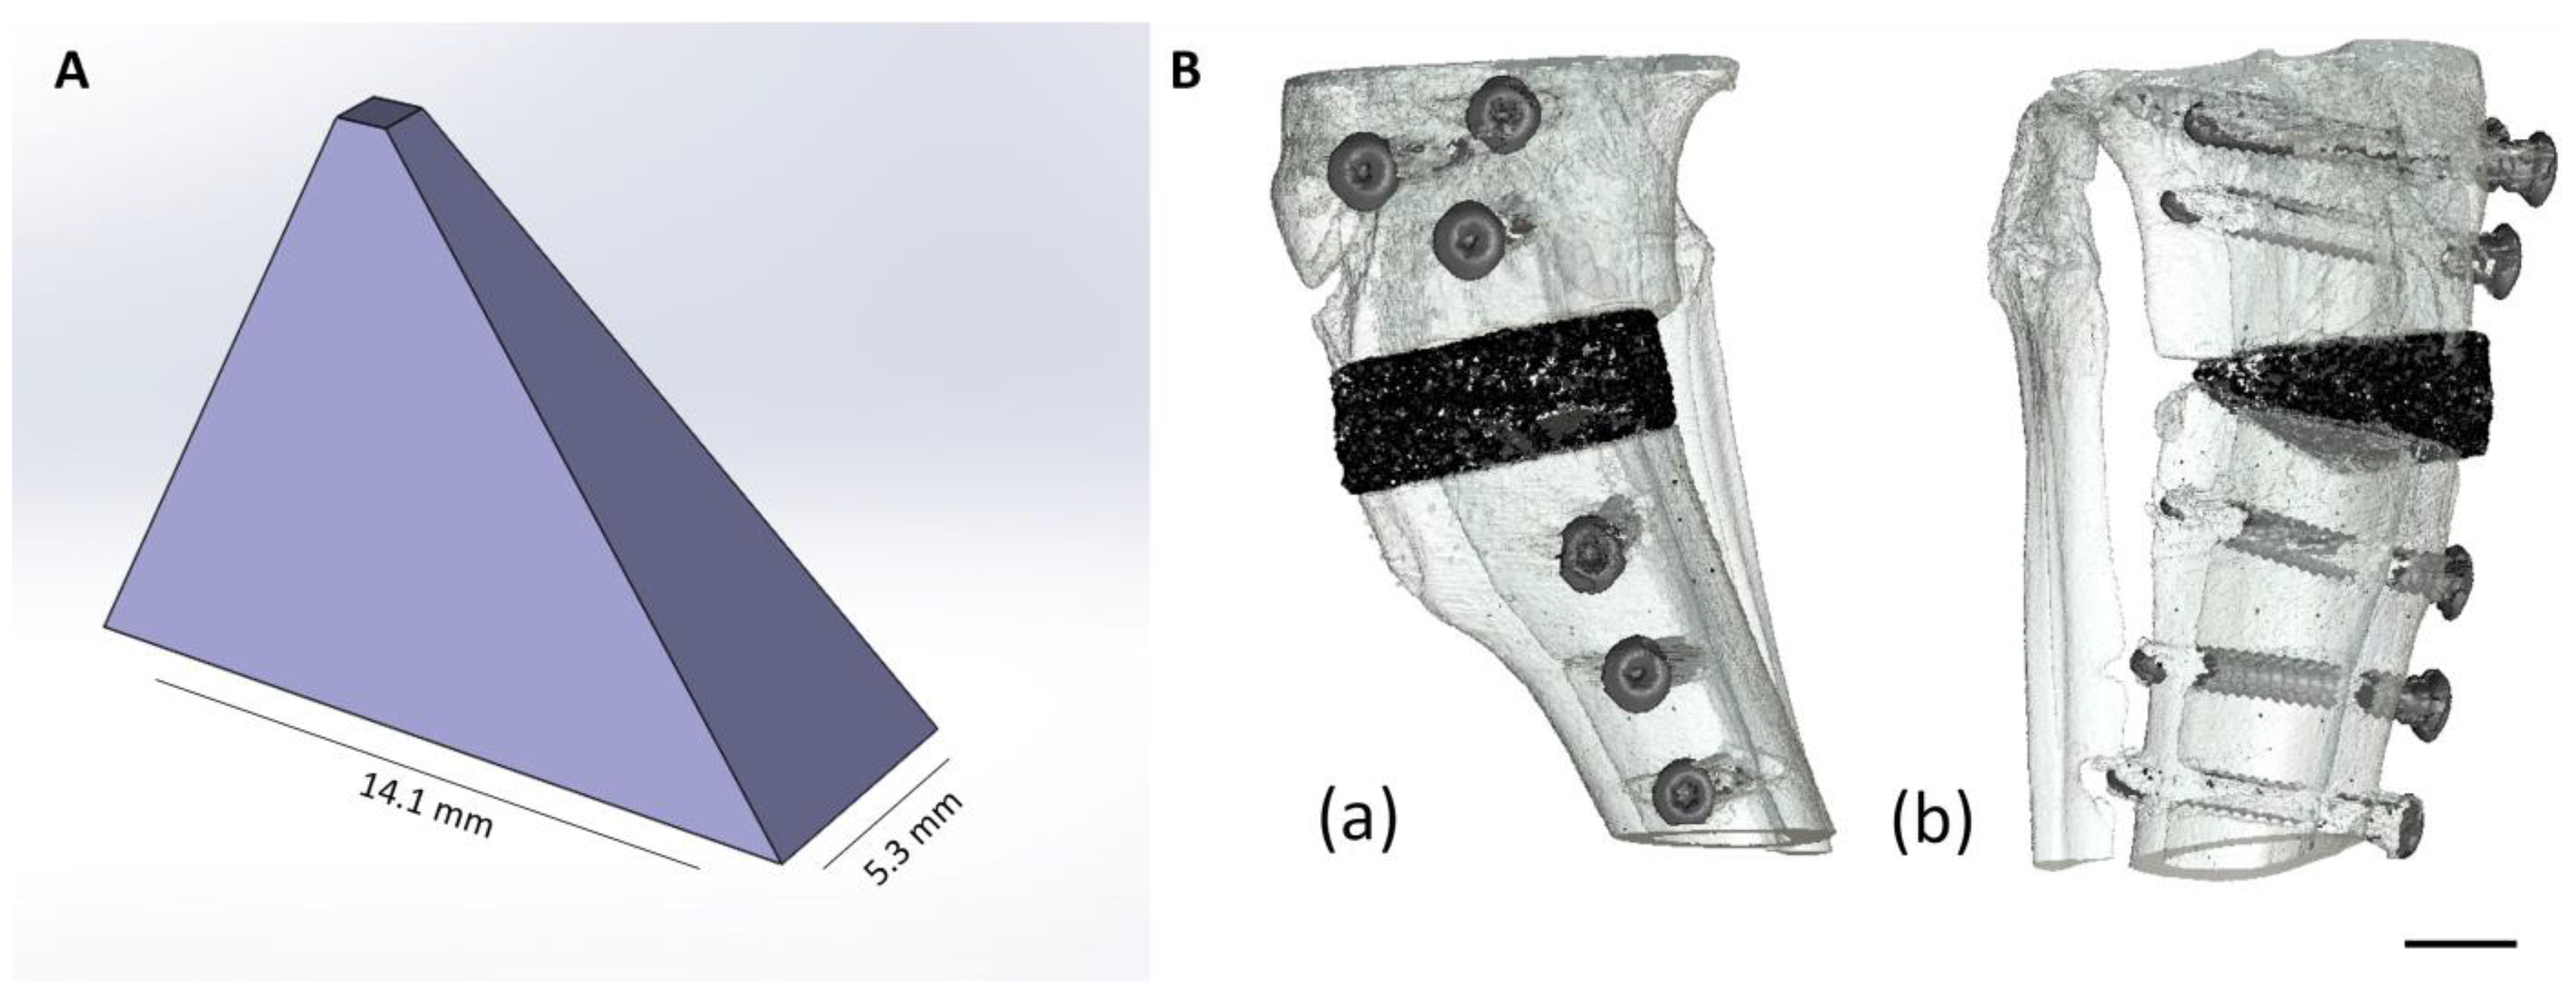

2.1.1. Production of the Scaffolds

2.2. Animal Model

2.2.1. Implantation of the Wedges